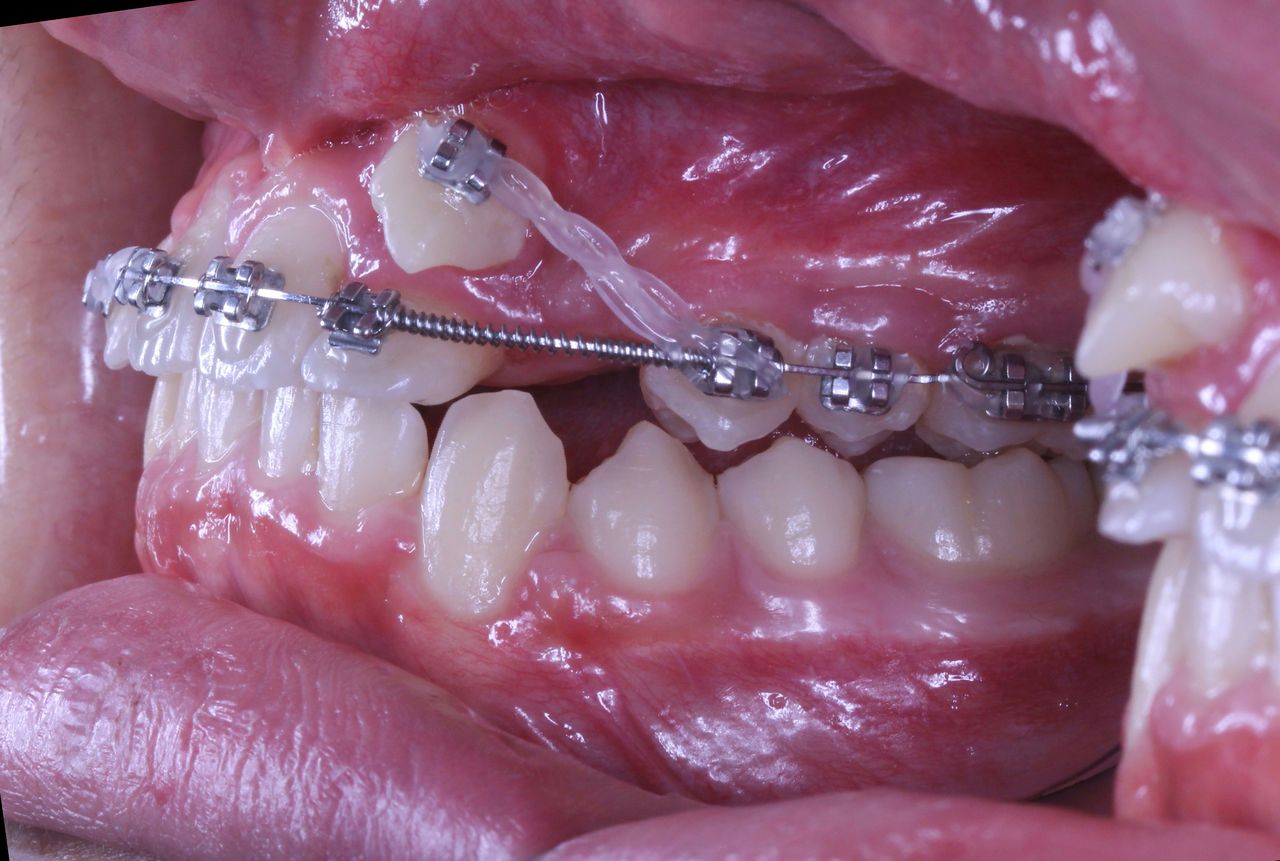

このように1番目と2番目の歯の間から犬歯3番目の歯が生えてきました。

また乳歯Cが残っているので 歯の順番でいうと

132Cという順番になっております

それを

132Cから Cを抜歯して 123という順番に並べなおすのです

大切なことは 歯を移動する際に それぞれの歯の根がぶつからないかどうか?ということと

歯茎の状態が歯の移動に耐えることができるかどうか?また十分な骨の量があるかどうかというところです。

現在の状況はもう少し治療が進んでいるのですが、矯正歯科ネットユーザー様からの質問が昨日でしたので、数か月前の記録ですが、現在の進行状況です

正面と側面の写真をみてもあまり変化がわからないと思います。